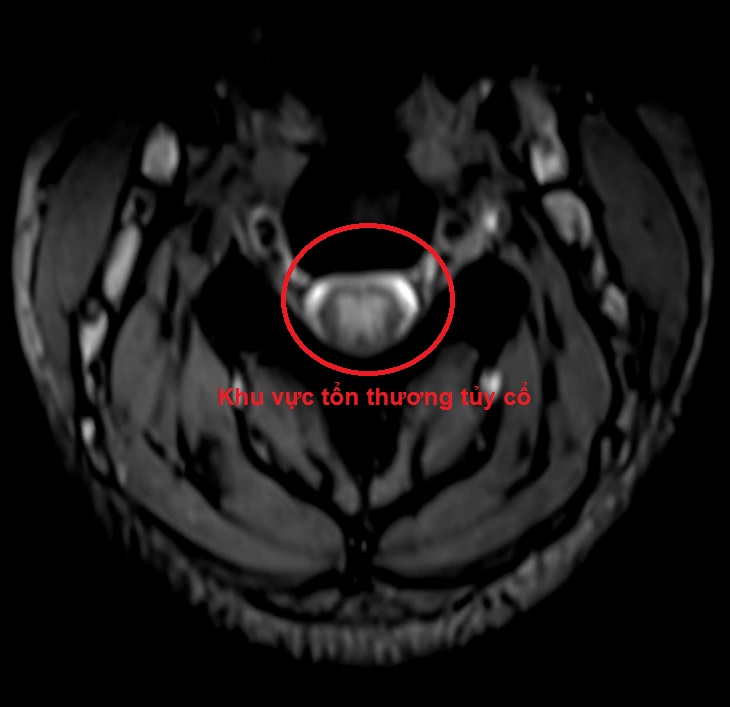

Kết quả chụp cộng hưởng từ (MRI 3.0) Cột sống cổ: tủy cổ ngang mức C2-C6 có tín hiệu tăng trên T2W-I và T2W-W.

Hình 1: Tổn thương tủy cổ trên phim MRI 3.0 cột sống cổ. Ảnh BVCC

Chính vì vậy, trên những người bệnh có triệu chứng tê bì, dị cảm tứ chi, việc khai thác tiền sử lạm dụng bóng cười, khám lâm sàng và cận lâm sàng đầy đủ, đặc biệt là MRI cột sống cổ và đo dẫn truyền thần kinh sẽ giúp cho việc chẩn đoán chính xác, từ đó sẽ phục hồi chức năng vận động của người bệnh một cách tối đa.